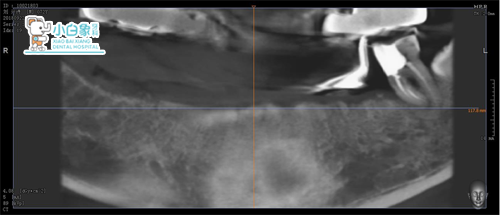

影像学检查见拔牙窝愈合良好

设计思路:33,35,43,46数字种植导板指导下精确种植